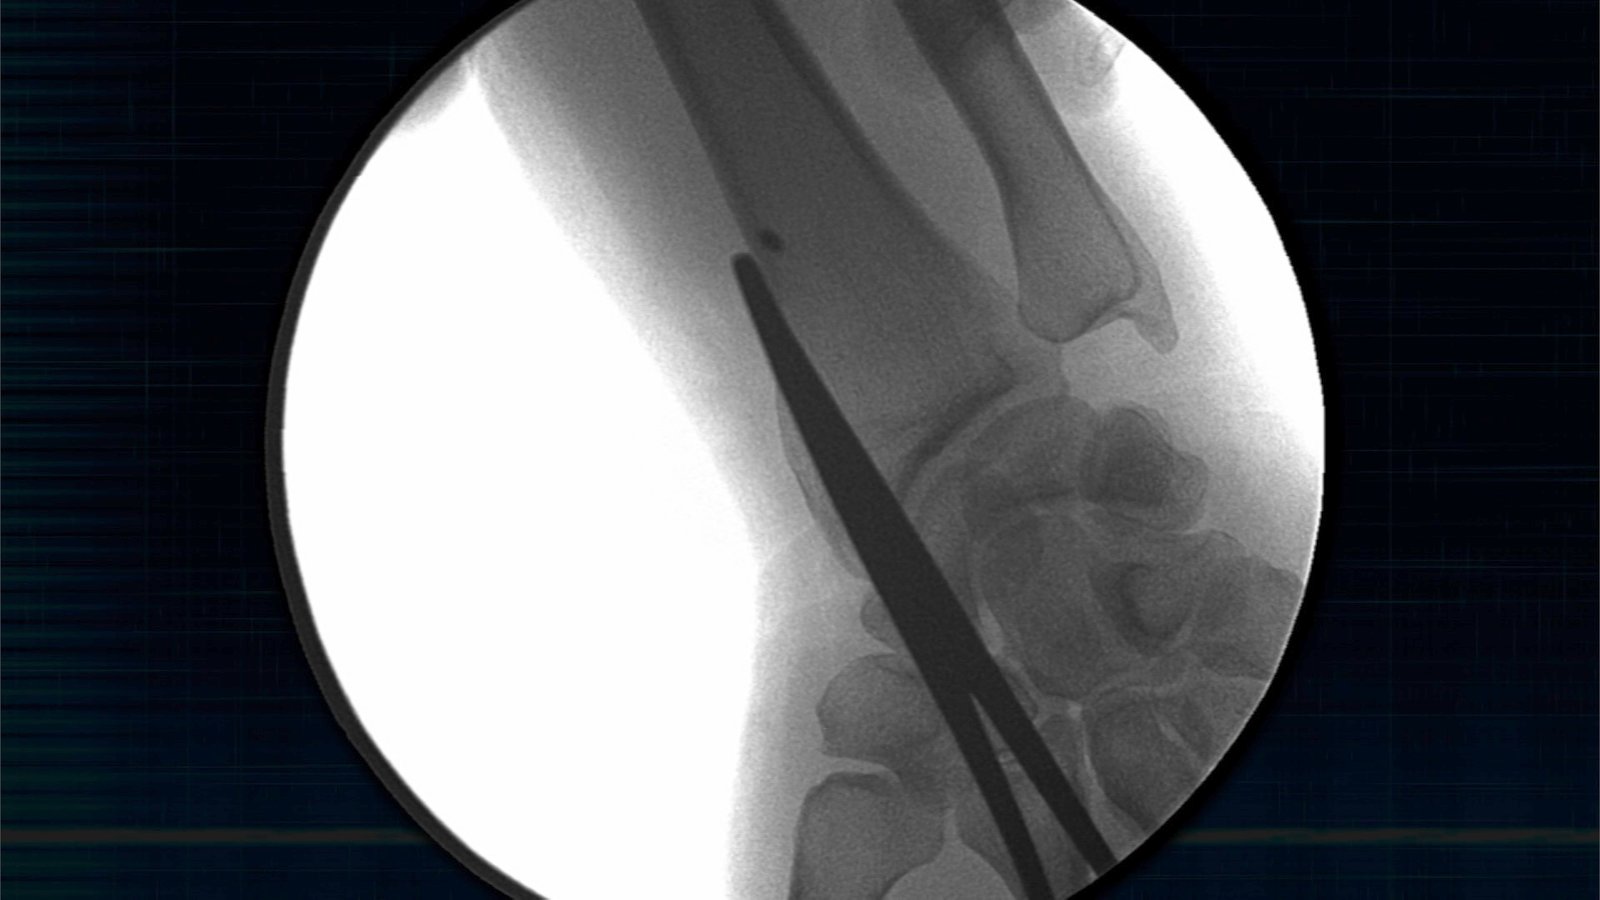

En el especial “LOS ABDUCIDOS”, que History estrena el próximo lunes 25 de abril, Maussan presenta tres supuestos casos de abducción. La primera historia es la de Ron Noel, un hombre de Florida posiblemente abducido de niño, que poseía un extraño implante dejado en su muñeca y que fue extraído quirúrgicamente ante la cámara. El instrumento foráneo transmitía señales hacia el espacio profundo. El segundo caso que presenta Maussan en este especial, que sucedió en los suburbios de Colorado, es el de Stan Romanek, quien asegura ser acosado por inteligencia militar y tiene evidencia y testigos de los fenómenos en torno a sus múltiples abducciones. Finalmente, LOS “ABDUCIDOS” cuenta la historia de Travis Walton, un leñador que relata cómo fue derribado por un haz de luz en las montañas de Arizona para reaparecer cinco días después. Su historia fue retrata en la película Hollywoodense de 1993 “Fire in the sky” (“Fuego en el cielo”).